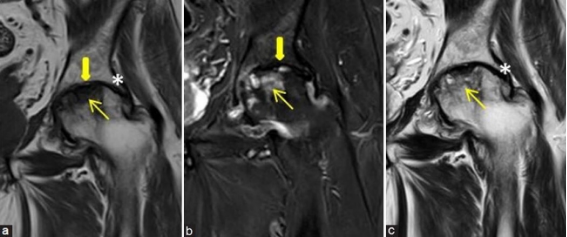

- Ressonância magnética (padrão-ouro para diagnóstico precoce)

A ressonância permite identificar lesões antes do colapso estrutural — momento ideal para intervenção preservadora.